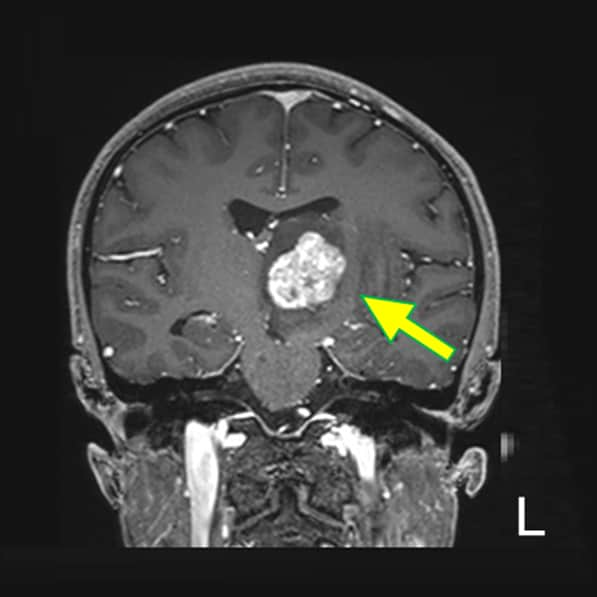

図6.造影後 T1WI (Cor.)

水平断同様に内部に小さな造影欠損を伴い、強く造影される病変を認める(矢印)。